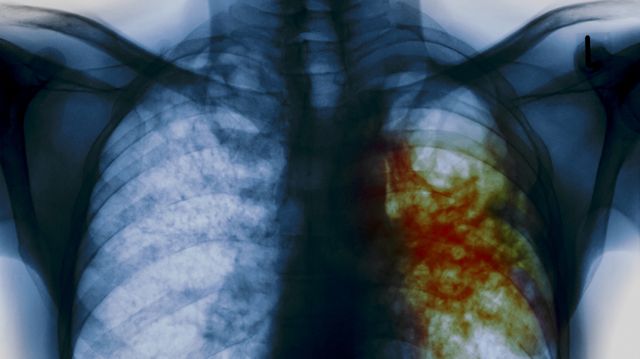

В Алапаевском районе вновь всплыла жуткая история, связанная с туберкулезом. Но на этот раз пострадать могли не коровы на ферме, а дети в школе, в которой полгода работал учитель с опасным заболеванием, перешедшим в открытую форму. Избежать эпидемии удалось лишь чудом, а родители узнали обо всем только после того, как у их детей тайно взяли кровь на анализ. Кроме того, до сих пор под угрозой находится здоровье троих педагогов и двоих детей.

На собрании местный фельдшер вместе с директором школы рассказали, что бывший учитель болеет открытой формой туберкулеза. Затем детям старше 15 лет пришлось пройти массово флюорографию, а остальным – сделать рентген легких. Кроме того, дети сдавали диаскинтест - более эффективный аналог пробы манту.

Сейчас ученики посещают школу в полном составе, очевидно, пока ни у кого не выявлена открытая форма туберкулеза. Но родителей это не успокаивает – неизвестно, что будет через полгода, ведь болезнь может проявиться позднее.